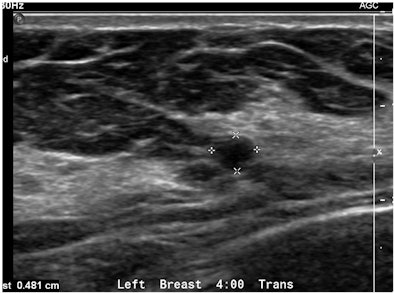

"A simple, yet powerful application of PDUS is differentiating between a rounded, markedly hypoechoic tumor and a [thickened] cyst with low-level internal echoes," he said. "The detection of the smallest vessel within the lesion automatically excludes a cyst -- or any other fluid collection -- and confirms a neoplasm. This very simple yet very useful application of PDUS is still underused."

| Images are of a circumscribed round pseudocystic mass. Above, grayscale US shows a cystic appearing mass with some low-level internal echoes. Below, PDUS performed with only minimal pressure applied through the probe shows internal vascularity, thereby excluding a fluid-filled lesion and confirming a tissular mass. Fine-needle aspiration readily confirmed a metastasis from a uterine leiomyosarcoma treated six years previously. All images courtesy of Dr. Bruno Fornage. |